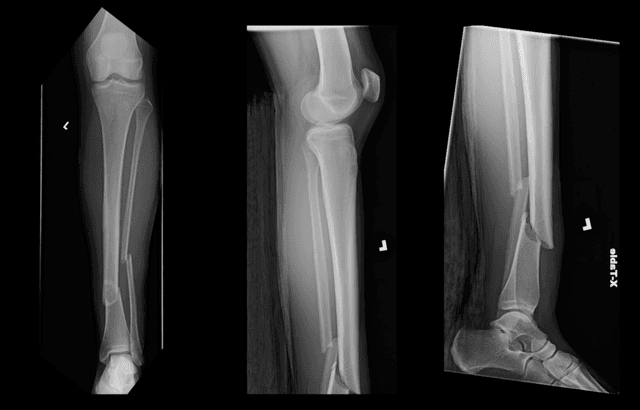

Pre-op